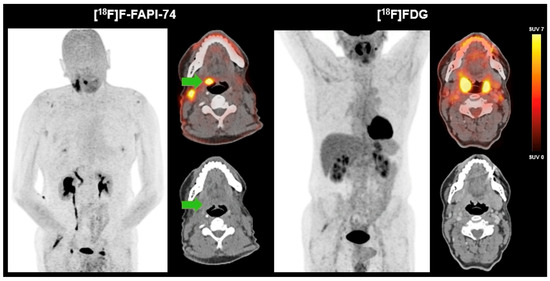

We present a 60-year-old male patient who presented with a two-year history of right-sided cervical soft tissue swelling. MRI revealed a well-circumscribed, spherical lesion in the right mandibular angle with cystic-regressive components and strong contrast enhancement. Furthermore, multiple enlarged lymph nodes were observed bilaterally in the mandibular angle and along the vascular nerve sheath. The enhancement of contrast in the right lingual tonsil was deemed to be reactive. The preliminary differential diagnosis included lymphoma. Surgical excision of the lesion revealed a partially cystic-necrotic lymph node metastasis (maximum diameter 4.7 cm) of a moderately differentiated, keratinizing SCC without extracapsular spread. The presence of strong p16 expression was indicative of a probable association with human papilloma virus, with the oropharynx being identified as the presumed primary site. As no definitive primary tumor could be identified on initial imaging or clinical examination, the case was classified as HNCUP. FDG-PET/CT revealed symmetrical metabolic activity in the Waldeyer’s ring and a suspicious FDG-avid lymph node in the left upper vascular nerve sheath, but no distinct FDG-avid primary lesion. Subsequent [18F]F-FAPI-74-PET/CT demonstrated focal FAP expression in the right palatine tonsil, raising suspicion of a tonsillar carcinoma, as well as increased FAPI uptake in correlation with postoperative changes following lymph node dissection. In contrast to FAPI-PET/CT, no morphologically distinct lesion could be delineated in the region of the right palatine tonsil on CT. No further evidence of a FAP-expressing malignancy was detected (Figure 1). Definitive histopathology of the excised right tonsil and right tongue base confirmed infiltrates of a non-keratinizing, p16-positive SCC (pT2, pN2a [1/18, 4.7 cm], L0, V0, Pn0), with all surgical margins being negative (R0).

Figure 1.

FAPI-PET/CT versus FDG-PET/CT in HNCUP.

In a 60-year-old male patient with HNCUP following lymph node excision of a partially cystic-necrotic lymph node metastasis of a moderately differentiated, keratinizing SCC without extracapsular spread, FDG-PET/CT showed no definitive evidence of a metabolically active primary tumor. There was diffusely increased but largely symmetrical FDG uptake in the Waldeyer’s ring and a single suspicious FDG-avid lymph node in the left upper cervical level along the vascular nerve sheath. In contrast, [18F]F-FAPI-74-PET/CT demonstrated focal, intense FAP expression in the right palatine tonsil (green arrow), suggestive of a primary tonsillar carcinoma. On CT, no morphologically distinct lesion could be delineated in the region of the right palatine tonsil, underlining the added diagnostic value of FAPI-PET in identifying the primary tumor site. Additionally, a diffuse FAPI uptake in the surgical bed following lymph node excision consistent with postoperative changes was detected. Definitive histopathology confirmed infiltrates of a non-keratinizing, p16-positive SCC.